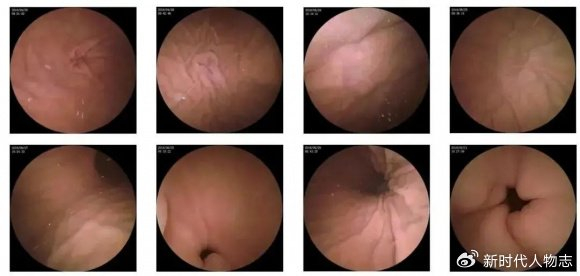

摘要:本文介紹了肛門息肉早期的圖片和相關介紹。肛門息肉是肛門部位的一種常見病變,早期發(fā)現(xiàn)對于治療具有重要意義。文章通過圖片展示了肛門息肉的早期形態(tài),并簡要介紹了其癥狀、原因、診斷和治療等方面的信息,以幫助人們更好地了解和認識這一疾病。

肛門息肉早期圖片展示

(請在此處插入肛門息肉早期圖片)

圖片展示可以幫助公眾更直觀地了解肛門息肉的外觀和癥狀,請注意,由于個體差異和拍攝角度等因素,圖片僅供參考,不能作為診斷依據(jù)。

2、內(nèi)窺鏡檢查:通過結腸鏡或直腸鏡檢查,可以清晰地觀察到腸道內(nèi)的息肉。